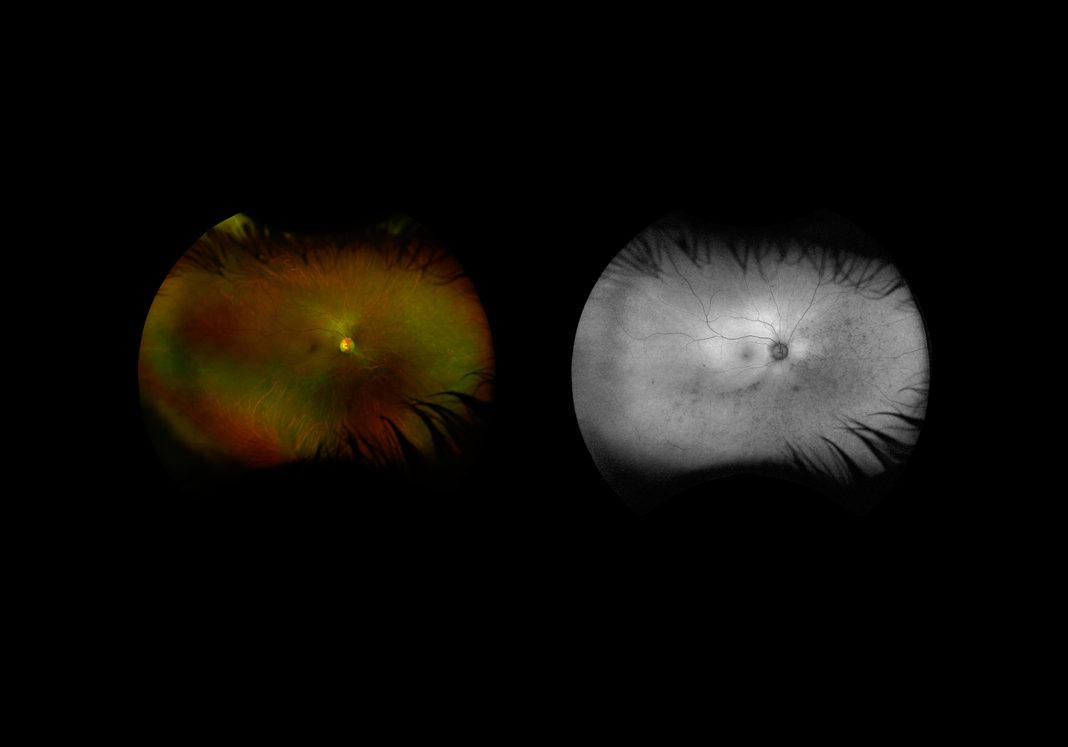

Dietro l’errore di traduzione e la spinta inebriante di una possibile scoperta, si nasconde un errore ancora più sorprendente: gli strumenti di osservazione utilizzati da Lowell e Schiaparelli funzionavano anche da dispositivo ottico, proiettando le strutture neurovascolari dei loro stessi occhi. I due scienziati non mappavano altro che le ombre dei propri vasi sanguigni e l’architettura della loro stessa retina. Non solo, osservavano ignari la loro stessa visione, erano in balia della loro percezione. Ed ecco che luci e ombre diventano punti, che si uniscono in linee, che si strutturano in diramazioni, che danno adito a teorie che ispirano romanzi come "La guerra dei mondi”, capaci di muovere masse di migliaia di americani, che nel 1938 ascoltando la trasmissione radiofonica di Halloween di Orson Welles temono davvero che i marziani siano sbarcati nel New Jersey.